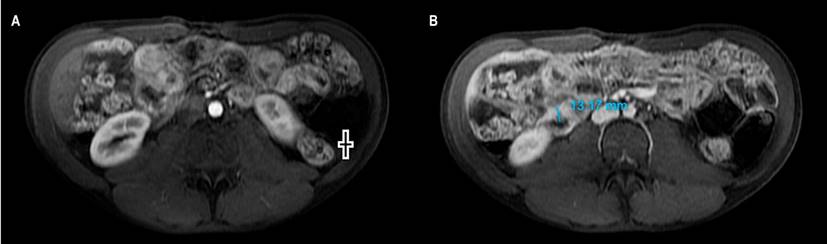

After 6 months, his respiratory and constitutional symptoms improved, but he was admitted to the hospital due to persistent abdominal pain and diarrhea. Adherence to antituberculous therapy was confirmed, and microbiological studies for TB were negative. The laboratory tests detected fecal calprotectin of 2,060 μg/g (Table 1) and the magnetic resonance enterography (MRE), intestinal sub-occlusion in the ileum (Figure 1). A new ileocolonoscopy identified cecal folds, appendiceal orifice, and ileocecal valve with severe edema covered by ulcers, easy bleeding, and edema involving the proximal ascending colon. In addition, biopsies were taken that reported inflammatory bowel disease with chronic ulceration and granulomas (Figure 2). The diagnosis of CD was made with a Crohn’s disease activity index (CDAI) of 421 points. Controversially, corticosteroids were postponed, starting treatment with azathioprine.

Figure 1 MRE with contrast. A. In the arterial phase: thickening of the ileus (+). B. In the portal phase: thickening of the ileum with a wall of 13 millimeters. Image owned by the authors.

Although controversial and reserved for very selected cases, when there is confusion between CD and TB in countries where TB is frequent, some authors recommend a therapeutic trial with anti-tuberculosis drugs to corroborate the clinical improvement at 3 months and healthy mucosa at 6 months in almost 100% of patients with TB10, which did not occur in this patient. In addition, the MRE, histopathology, and laboratory findings, such as elevated fecal calprotectin (with approximate sensitivity and specificity of 90% and 80%, respectively)11,12 allowed the diagnosis of CD.